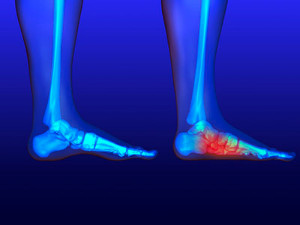

Doctors often perform two tests – blood tests and x-rays – when trying to diagnose bunions, especially in the early stages of development. Blood tests help determine if the foot pain is being caused by something else, such as arthritis, while x-rays provide a clear picture of your bone structure to your doctor.

Your podiatrist will diagnose your bunion by doing a thorough examination of your foot. He or she may also conduct an x-ray to determine the cause of the bunion and its severity.

Heel pain, a common ailment, can be a source of discomfort that interferes with daily activities. The causes of heel pain can vary, with one of the most prevalent being plantar fasciitis. This condition involves inflammation of the plantar fascia, the thick band of tissue that supports the arch of the foot. Other common culprits include Achilles tendonitis, heel spurs, and bursitis. The good news is that heel pain is often treatable. Treatment options for heel pain range from conservative methods to more advanced interventions. Resting and performing gentle stretching exercises can provide relief, while custom-made orthotics may help distribute pressure more evenly. In severe or persistent cases, minimally invasive procedures such as corticosteroid injections may be recommended. Consulting a podiatrist is crucial in determining the underlying cause, in addition to guiding you toward the most suitable treatment plan. By addressing the root cause and following a tailored treatment regimen, you can take significant steps towards a pain-free and active lifestyle. It is strongly suggested that you visit a podiatrist who can accurately diagnose the cause for your heel pain and treat it accordingly.

Heel pain is often associated with plantar fasciitis. The plantar fascia is a band of tissues that extends along the bottom of the foot. A rip or tear in this ligament can cause inflammation of the tissue.

Achilles tendonitis is another cause of heel pain. Inflammation of the Achilles tendon will cause pain from fractures and muscle tearing. Lack of flexibility is also another symptom.

Heel spurs are another cause of pain. When the tissues of the plantar fascia undergo a great deal of stress, it can lead to ligament separation from the heel bone, causing heel spurs.

Heel pain should be treated as soon as possible for immediate results. Keeping your feet in a stress-free environment will help. If you suffer from Achilles tendonitis or plantar fasciitis, applying ice will reduce the swelling. Stretching before an exercise like running will help the muscles. Using all these tips will help make heel pain a condition of the past.

Have you ever gotten up from a chair or out of bed in the morning, and upon taking that first step, feel like your heel has stepped on a tack? Many people experience a feeling of sharp pain which radiates into their arch from their heel and which does not allow them to put their heel on the floor. Sometimes they need to sit back down, stand only on their toes and use the wall for balance. If you can take a few steps, it seems to go away and lessen, allowing you to then resume your activity. Later, throughout your day and after a period of rest, it can happen again. If this sounds familiar you may be suffering from your first attack of heel pain.

Heel pain is a debilitating condition that affects day to day activities. Running and walking both causes stress on the heel because the heel is the part of the foot that hits the ground first. This means that the heel is taking on your entire weight. Diagnosis and treatments for heel pain can be easily found through your podiatrist.

Plantar Fasciitis

One of the main causes of heel pain is a condition known as plantar fasciitis. The plantar fascia is a band of tissue that extends along the bottom of the foot, from the toe to the bottom of the heel. A rip or tear in this ligament can cause inflammation of these tissues, resulting in heel pain. People who do not wear proper fitting shoes are often at risk of developing problems such as plantar fasciitis. Unnecessary stress from ill-fitting shoes, weight change, excessive running, and wearing non-supportive shoes on hard surfaces are all causes of plantar fasciitis.

Achilles Tendonitis

Achilles tendonitis is another cause of heel pain. Similar to plantar fasciitis, inflammation of the Achilles tendon will cause heel pain due to stress fractures and muscle tearing. A lack of flexibility of the ankle and heel is an indicator of Achilles tendonitis. If left untreated, this condition can lead to plantar fasciitis and cause even more pain on your heel.

Heel Spur

A third cause of heel pain is a heel spur. A heel spur occurs when the tissues of the plantar fascia undergo a great deal of stress, leading to a separation of the ligament from the heel bone entirely. This results in a pointed fragment of bone on the ball of the foot, known as a heel spur.